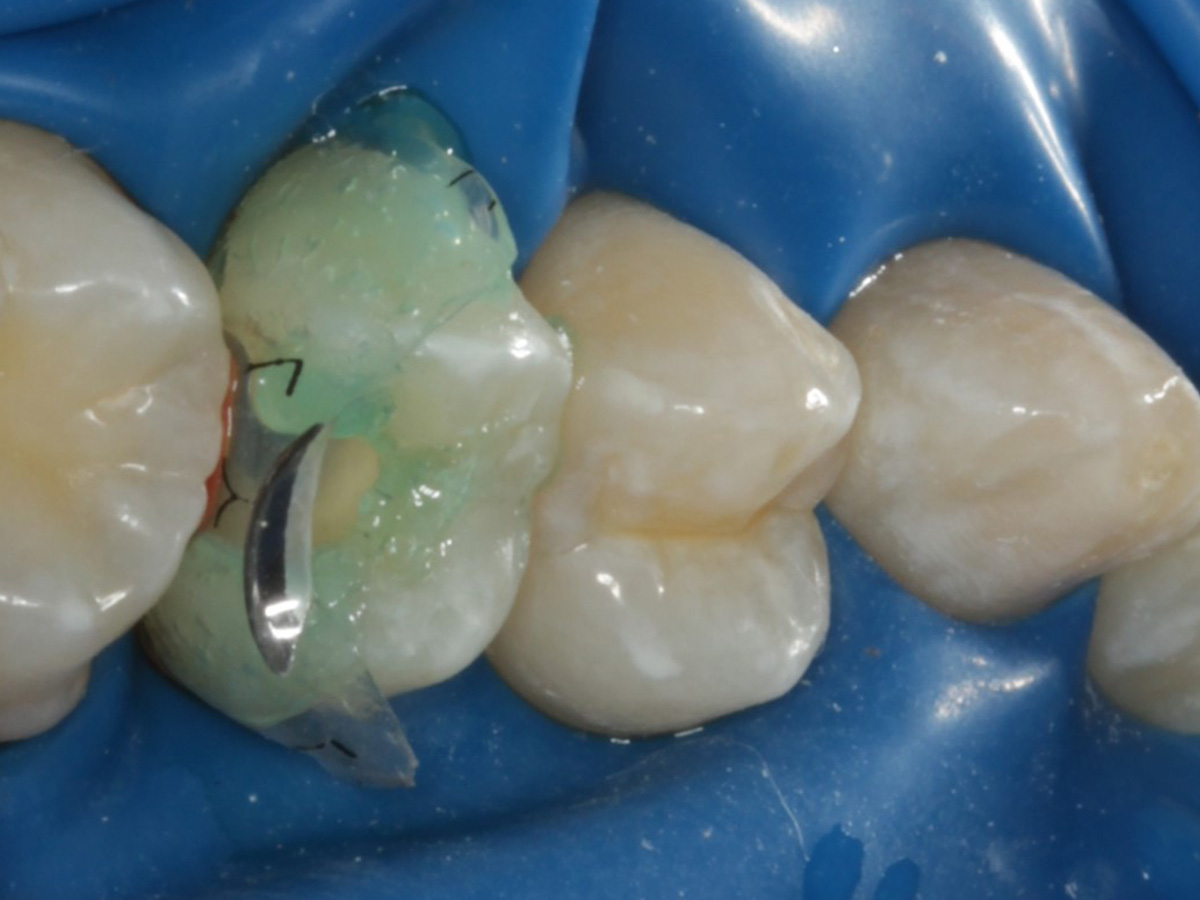

Abbildung 10

Nach Spray und Trocknung der Kavität: perfekte Adaptation der Matrize insbesondere tief subgingival